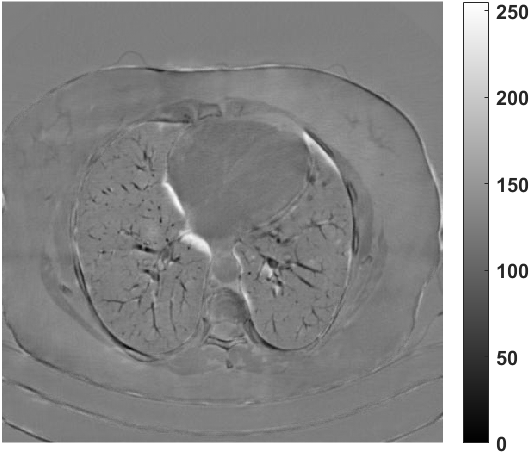

Fig. 4 presents the reconstruction results and residual images obtained by different methods for limited-angle reconstruction. As can be seen, the learning-based methods outperform the direct method and TV model, which exhibit serious artifacts in the missing angle region. Although the denoiser introduced by the FBP-Unet can somehow deal with the noises, the result still presents obvious artifacts. Compared to the SIPID, PD-net and FSR-nets, our LRIP-net1/2 can better preserve the image details and edges with less information left in the residual images. Thus, both the quantitative and qualitative results confirm that the low-to-high double-resolution strategy can improve the reconstruction accuracy for the limited-angle reconstruction problem.

We observe that the low-resolution image prior plays an important role in our method. More specifically, we compare the results of our LRIP-net with respect to different low-resolution priors, which are obtained by down-sampling rate of 1/2, 1/4, and 1/8, respectively. As can be seen in Table III, the best reconstruction results are obtained with the image prior reconstructed by the down-sampling rate of for 150∘, 120∘ and 90∘ limited-angle reconstruction. The visual comparison based on different image priors are also provided in Fig. 5, where obviously less artifacts are left in the reconstruction image by LRIP-net1/8. By comparing the running time, it is easy to see that the smaller the low-resolution image prior, the faster the LRIP-net works.